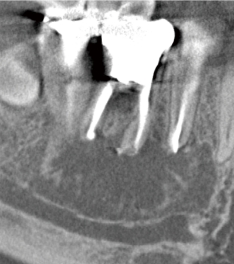

歯髄の焼灼、根管内外の感染組織や汚染物質の焼灼が行え、歯肉切除用のモードを選択することで、電気メスとしても使用可能です。

高周波通電により、チップ電極の先端部と接触した部位を発熱させることで、組織の焼灼・凝固・切開を行うことができます。

根管長測定機能によって根管内のチップ電極の位置を設定し、フットスイッチを踏むことで1秒間のHFCが行えます。

2タイプのチップ電極を付属。どちらでも根管長測定、HFCが行えます。